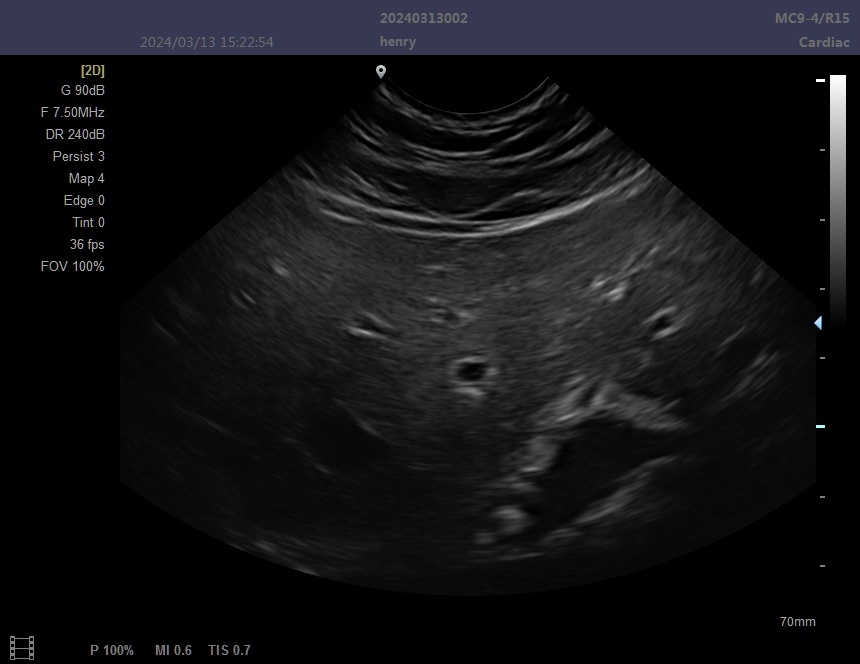

4)Support:3D imaging

5)Support probe:Convex\Linear\Cavity\Micro-convex\Rectal

6)Display Modes:B,B/B,4B,B+M,M, PW,B+PW

13)Frequency Conversion:Support operating frequency according to the probe application, frequency range:2-12MHz